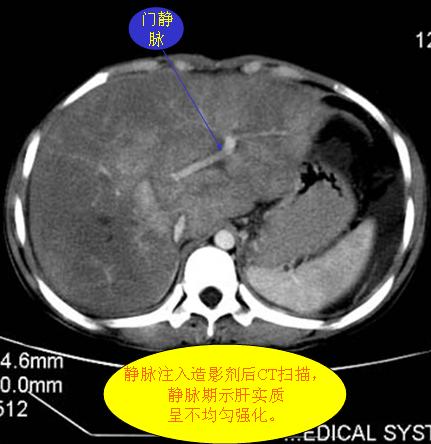

腹部ct解剖与基本病变